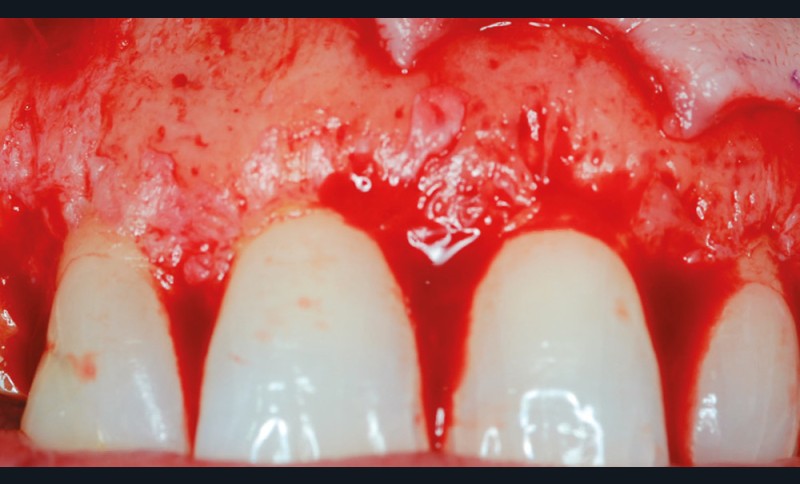

2 – L’élongation coronaire se fera aux dépens du parodonte superficiel et du parodonte profond. Une gingivectomie n’est possible que si le parodonte comporte plus de 3 mm de gencive kératinisée. En effet, il est recommandé…